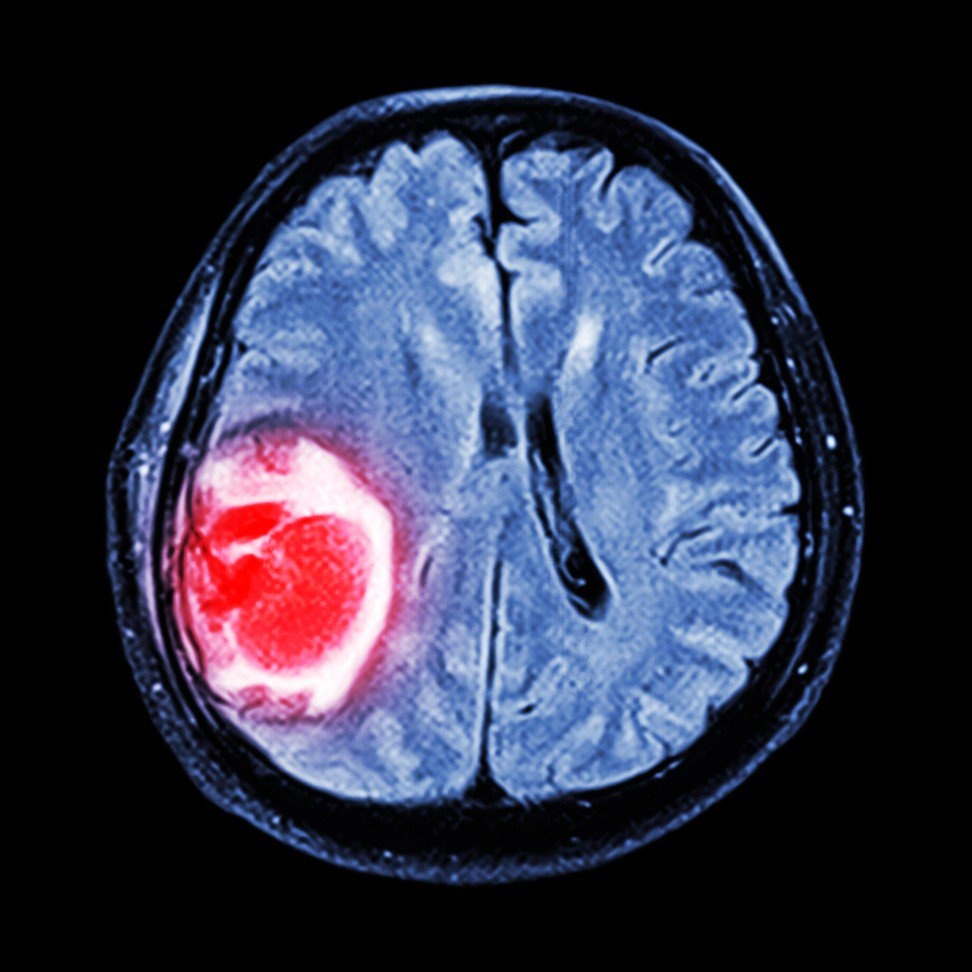

Công nghệ này, được gọi là hình ảnh cộng hưởng từ, có thể giúp nghiên cứu hoặc chẩn đoán các tình trạng thoái hóa thần kinh bao gồm bệnh Parkinson và bệnh Alzheimer.

| Hình ảnh cộng hưởng từ có thể được sử dụng để nghiên cứu và chẩn đoán tình trạng thoái hóa thần kinh như bệnh Parkinson và Alzheimer. Ảnh: Alamy. |